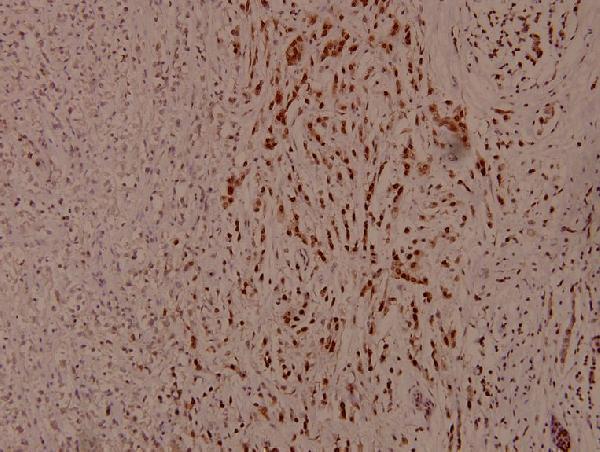

Facts about Aurora kinase A.

Required for initial activation of CDK1 in centrosomes. Phosphorylates numerous target proteins, such as ARHGEF2, BORA, BRCA1, CDC25B, DLGP5, HDAC6, KIF2A, LATS2, NDEL1, PARD3, PPP1R2, PLK1, RASSF1, TACC3, p53/TP53 and TPX2.

Highly expressed in testis and weakly in skeletal muscle, thymus and spleen. Also highly expressed in colon, ovarian, prostate, neuroblastoma, breast and cervical cancer cell lines.

Cytoplasm, cytoskeleton, microtubule organizing center, centrosome. Cytoplasm, cytoskeleton, spindle pole. Cytoplasm, cytoskeleton, cilium basal body. Cytoplasm, cytoskeleton, microtubule organizing center, centrosome, centriole. Cell projection, neuron projection. Detected at the neurite hillock in developing neurons (By similarity). Localizes at the centrosome in mitotic cells from early prophase until telophase, but also localizes to the spindle pole MTs from prophase to anaphase (PubMed:9606188, PubMed:17229885, PubMed:21225229). Colocalized with SIRT2 at centrosome (PubMed:22014574). Move